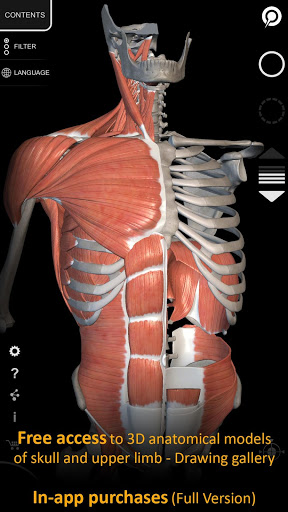

"Anatomy 3D Atlas" дозволяє легко та інтерактивно вивчати анатомію людини.

Завдяки простому та інтуїтивно зрозумілому інтерфейсу можна спостерігати кожну анатомічну структуру під будь-яким кутом.

Анатомічні 3D-моделі особливо деталізовані та мають текстури з роздільною здатністю до 4k.

"Anatomy - 3D Atlas" - це програма, призначена для студентів-медиків, лікарів, фізіотерапевтів, фельдшерів, медсестер, спортивних тренерів і всіх, хто зацікавлений у поглибленні своїх знань з анатомії людини.

Ця програма є фантастичним інструментом, який доповнює класичні книги з анатомії людини.

АНАТОМІЧНІ 3D МОДЕЛІ

• Кістково-м’язова система